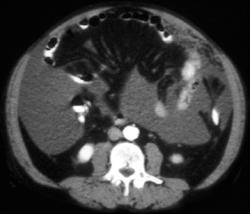

Antral Cancer and Carcinomatosis